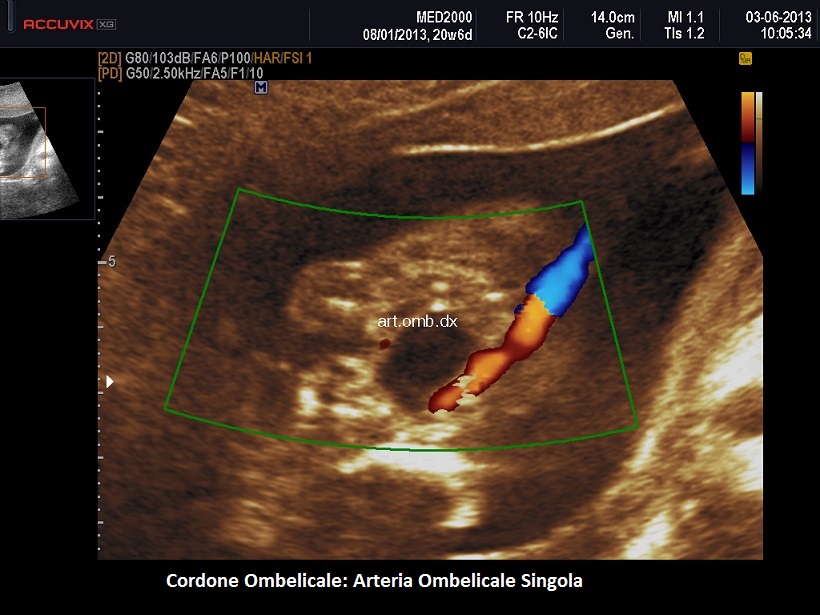

Arteria Ombelicale Singola (SUA -Single Umbilical Artery)

Arteria ombelicale singola (SUA - SINGLE UMBILICAL ARTERY)

Il cordone ombelicale presenta normalmente tre vasi: una vena e due arterie, destra e sinistra. L'Arteria ombelicale singola (SUA) è una anomalia del sistema vascolare del feto in cui manca una delle due arterie.

Il segno ecografico caratteristico è la presenza di due soli vasi nel cordone ombelicale. Al color-Doppler si osserva un solo vaso lateralmente alla vescica. In scansione trasversa si osserva un cordone con due soli vasi. Spesso l'unica arteria presente nel cordone va incontro ad una dilatazione compensatoria e mostra un calibro superiore ai 4 mm.; anche gli indici di resistenza risultano al di sotto della media per l'epoca gestazionale.

Diagnosi ecografica: Visualizzazione di una sola arteria attorno alla vescica fetale.